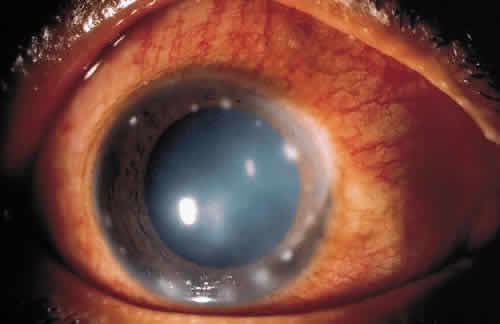

Cell-mediated immunity also plays an important role locally and systemically in the eye's defense against microorganisms. When a T lymphocyte becomes sensitized to a bacterial antigen, it releases a soluble factor (lymphokine) that can invest the macrophage with the power to destroy ingested organisms. The sensitized T lymphocyte also releases factors that can aggregate macrophages at the site of insult and hinder their departure from the site. Chemotactic factors for neutrophils, basophils, and eosinophils are also released.2 The leukocyte infiltrate may confine the pathogen and prevent its entrance into the interior of the eye, but may also contribute to the necrotizing inflammation of the corneal stroma seen in gram-negative bacteria and herpes simplex virus (HSV).20